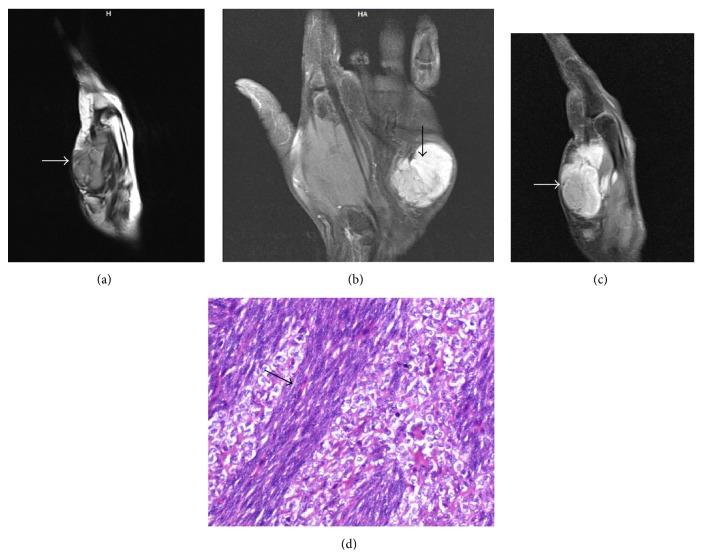

Aim. To evaluate soft tissue masses of the hand with magnetic resonance imaging (MRI) and ultrasonography (USG) and to correlate imaging findings with pathological findings. Material and Methods. Thirty-five patients with soft tissue masses of the hand were evaluated with high resolution USG and contrast enhanced MRI of the hand, prospectively over a period of 2.5 years. The radiological diagnosis was then compared with cytology/histopathology. Results. There were a total of 19 (55%) females. The mean age was 27.45 ± 14.7 years. Majority (45%) of cases were heteroechoic. Four cases were predominantly hyperechoic. These were later diagnosed as lipomas. Four cases were anechoic (diagnosed as ganglions). Only four lesions showed hyperintense signal on T1-weighted images. Out of these, 3 were lipomas and one was cavernous haemangioma. Three lesions were hypointense on T2-weighted images. All these lesions were diagnosed as giant cell tumor of the tendon sheath. A correct diagnosis was possible on MRI in 80% of cases (n = 28). Conclusion. MRI provides specific findings for diagnosis of certain soft tissue lesions of the hand. Ultrasonography allows accurate diagnosis of hemangioma/vascular malformations. However, in most conditions, imaging findings are nonspecific and diagnosis rests on pathologic evaluation.

目的。通过磁共振成像(MRI)和超声检查(USG)评估手部软组织肿块,并将影像学表现与病理结果进行关联。材料与方法。在2.5年的时间里,对35例手部软组织肿块患者进行前瞻性研究,采用高分辨率USG和手部对比增强MRI进行评估。然后将放射学诊断与细胞学/组织病理学结果进行比较。结果。共有19例(55%)女性。平均年龄为27.45±14.7岁。大多数病例(45%)为混合回声。4例主要为高回声,后来诊断为脂肪瘤。4例为无回声(诊断为腱鞘囊肿)。只有4个病灶在T1加权图像上表现为高信号,其中3个为脂肪瘤,1个为海绵状血管瘤。3个病灶在T2加权图像上表现为低信号,所有这些病灶均诊断为腱鞘巨细胞瘤。80%的病例(n = 28)通过MRI可做出正确诊断。结论。MRI为手部某些软组织病变的诊断提供了特异性表现。超声检查可准确诊断血管瘤/血管畸形。然而,在大多数情况下,影像学表现是非特异性的,诊断依赖于病理评估。